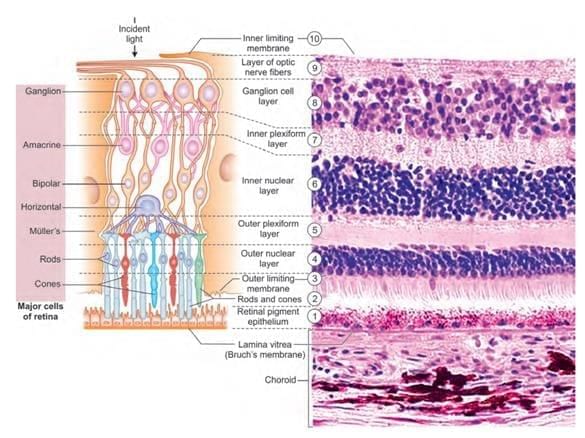

Which layer maintains hydration of corneal stroma? (NEET-PG 2020p)

Identify the marked layer in the given histological section: (AIIMS Nov 2019)